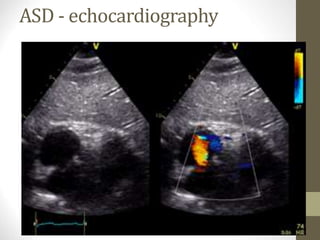

ASD - echocardiography

Atrial septal defect -